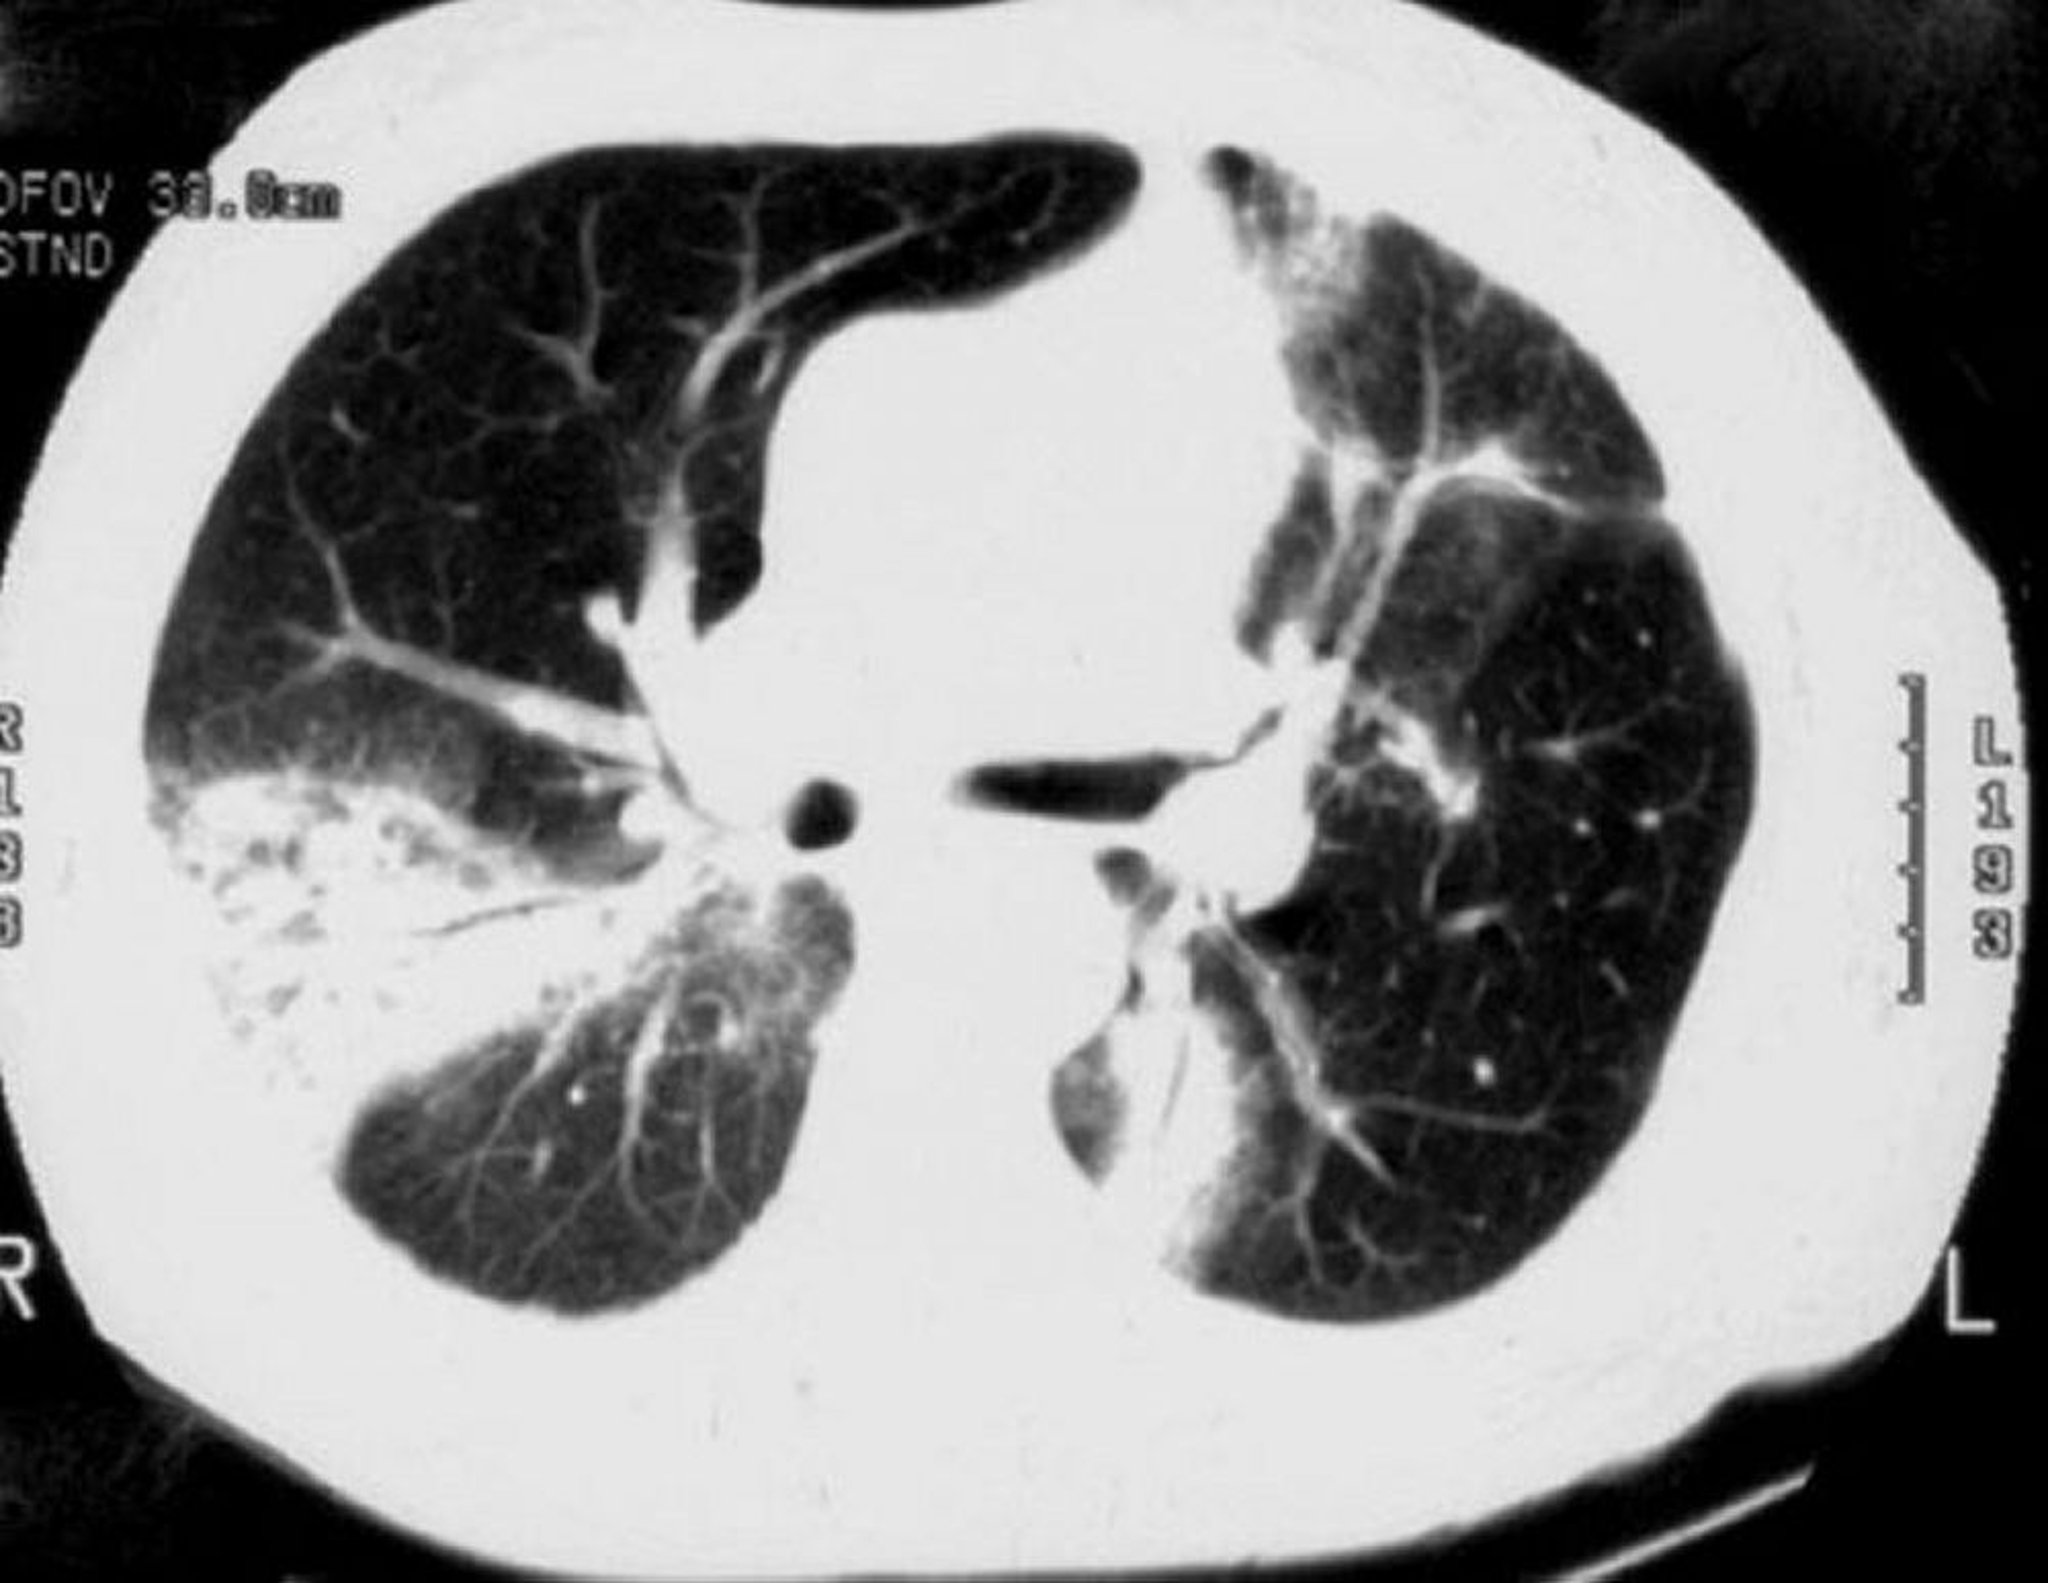

HRCT of the lung shows patchy airspace consolidation (present in 90% of patients), ground-glass opacities, small nodular opacities, and bronchial wall thickening and dilation. The patchy opacities are more common in the periphery of the lung, often in the lower lung zone. HRCT may show much more extensive disease than is expected from review of the chest radiograph. Small pleural effusions may be noted. The reversed halo sign (rim of consolidation with central clearing) is rare but appears to be relatively specific for organizing pneumonia.

Recovery after treatment is common when cryptogenic organizing pneumonia appears on HRCT as parenchymal consolidation, ground-glass opacity, or nodules. In contrast, recovery is less common when cryptogenic organizing pneumonia appears on HRCT as linear and reticular opacities.